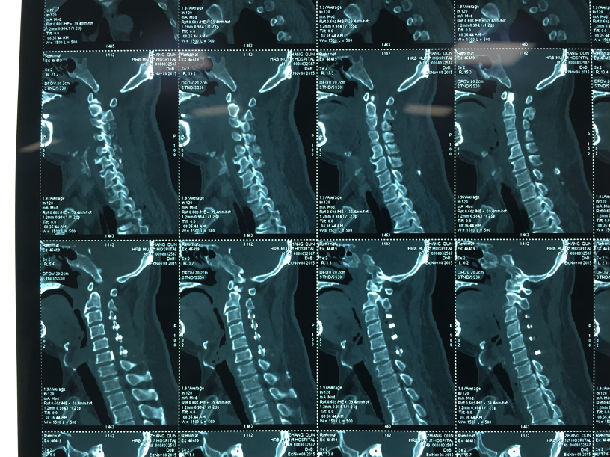

手术前-多节段颈椎间盘突出/黄韧带肥厚/颈椎管狭窄-脊髓损伤

手术前-颈髓明显受压伴脊髓损伤

显微镜下微创手术后-颈椎管明显增宽/脊髓受压解除/患者症状迅速好转